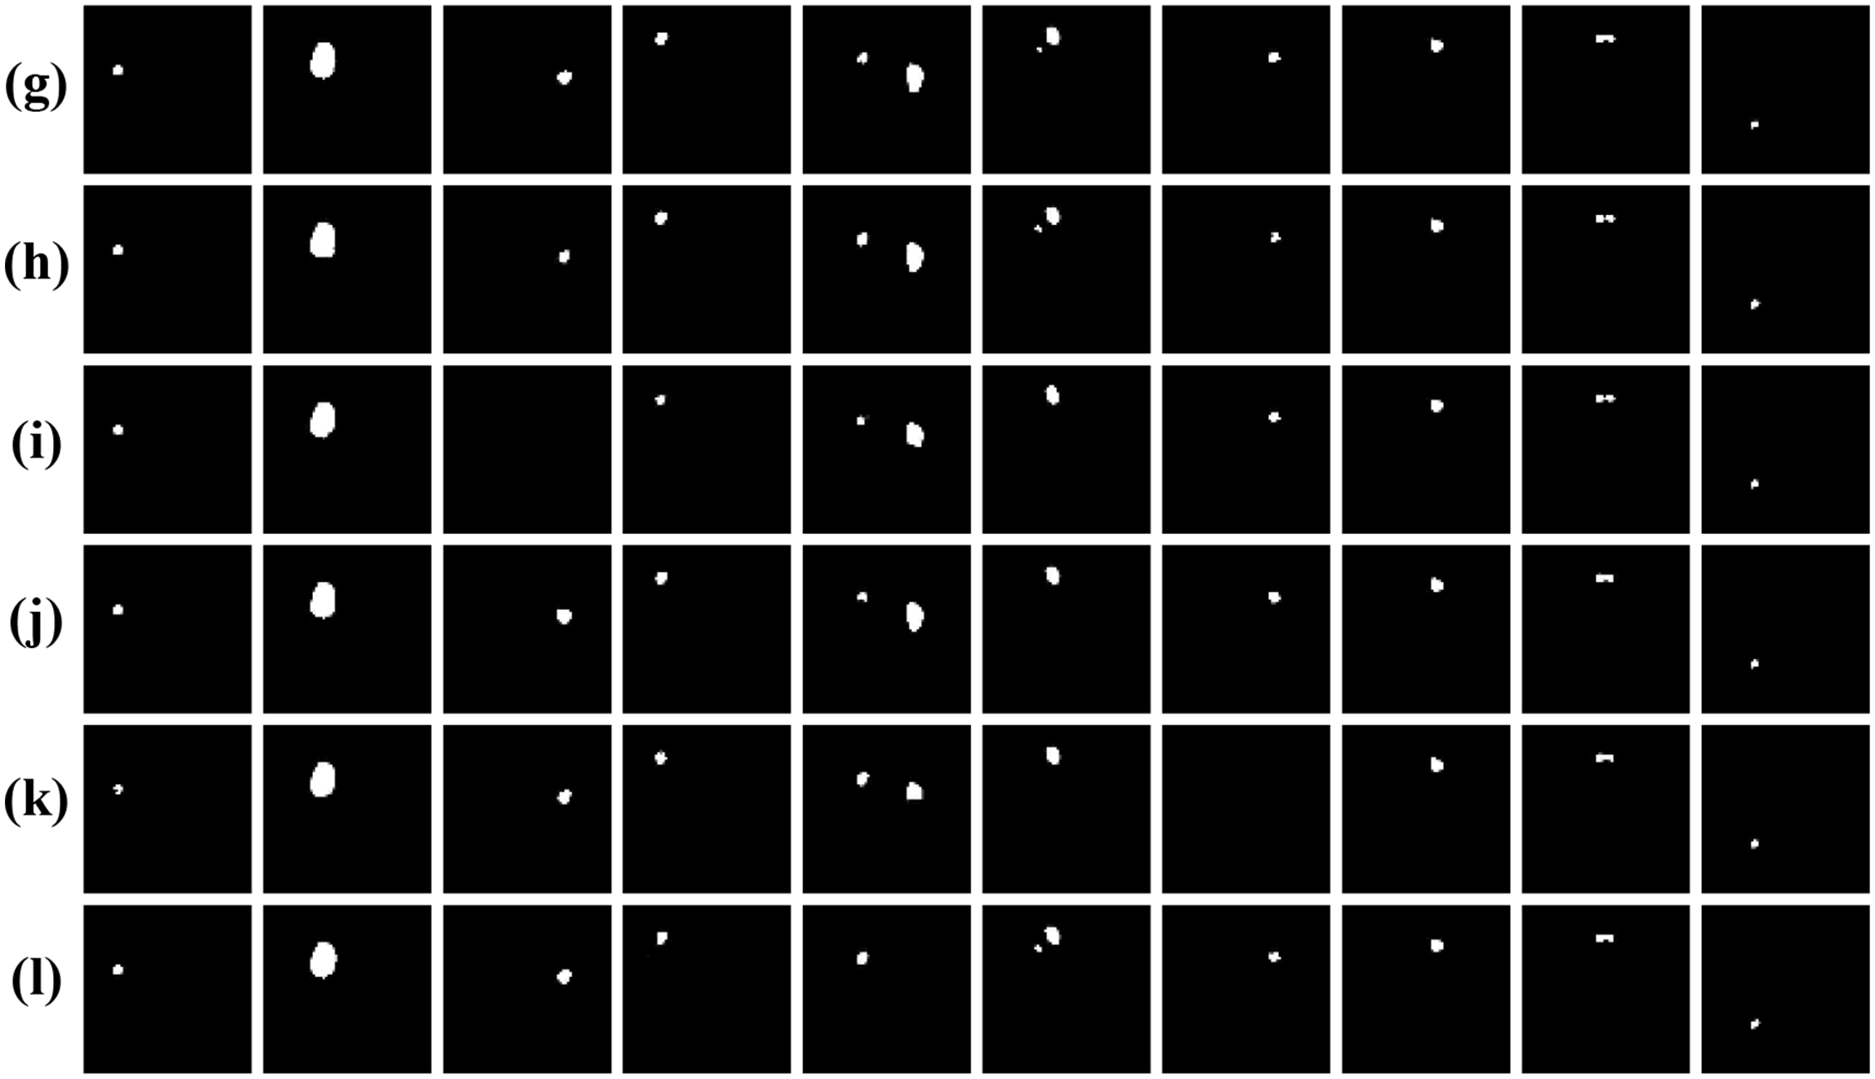

To further assess the generalization and robustness of our proposed method, we conducted comprehensive experiments on the jaw cyst dataset. This dataset poses unique challenges, such as small lesion sizes, low contrast boundaries, and anatomical variations across patients. Table 6 presents a detailed quantitative comparison of our proposed model with several classic segmentation networks, while Fig. 12 presents visual comparison of the results. From the metrics in Table 6, it is evident that our proposed method significantly outperforms all competing models, achieving the highest IoU of 0.8502 and Dice coefficient of 0.9188. These scores clearly demonstrate the method’s superior segmentation accuracy and how closely its outcomes match the ground truth masks, even in challenging images. As observed in the original cone-beam computed tomography slices and corresponding ground truth masks, the cyst regions are often small, low contrast, and embedded in complex jaw structures. Notably, our proposed method exhibits the highest fidelity in segmenting cyst regions, accurately capturing both the shape and size of the lesions with minimal false positive rates. In summary, both the quantitative results in Table 6 and the visual comparisons in Fig. 12 strongly affirm the effectiveness of our proposed method.

Figure 12: Visual comparison of different networks on the jaw cyst dataset: (a) Original images; (b) Label images; (c) U-Net; (d) ODsegmentation; (e) CLCI-Net; (f) BCDU-Net; (g) Connected-UNets; (h) MPSU-Net; (i) PMENet; (j) FF-UNet; (k) BiDFDC-Net; (l) The proposed method